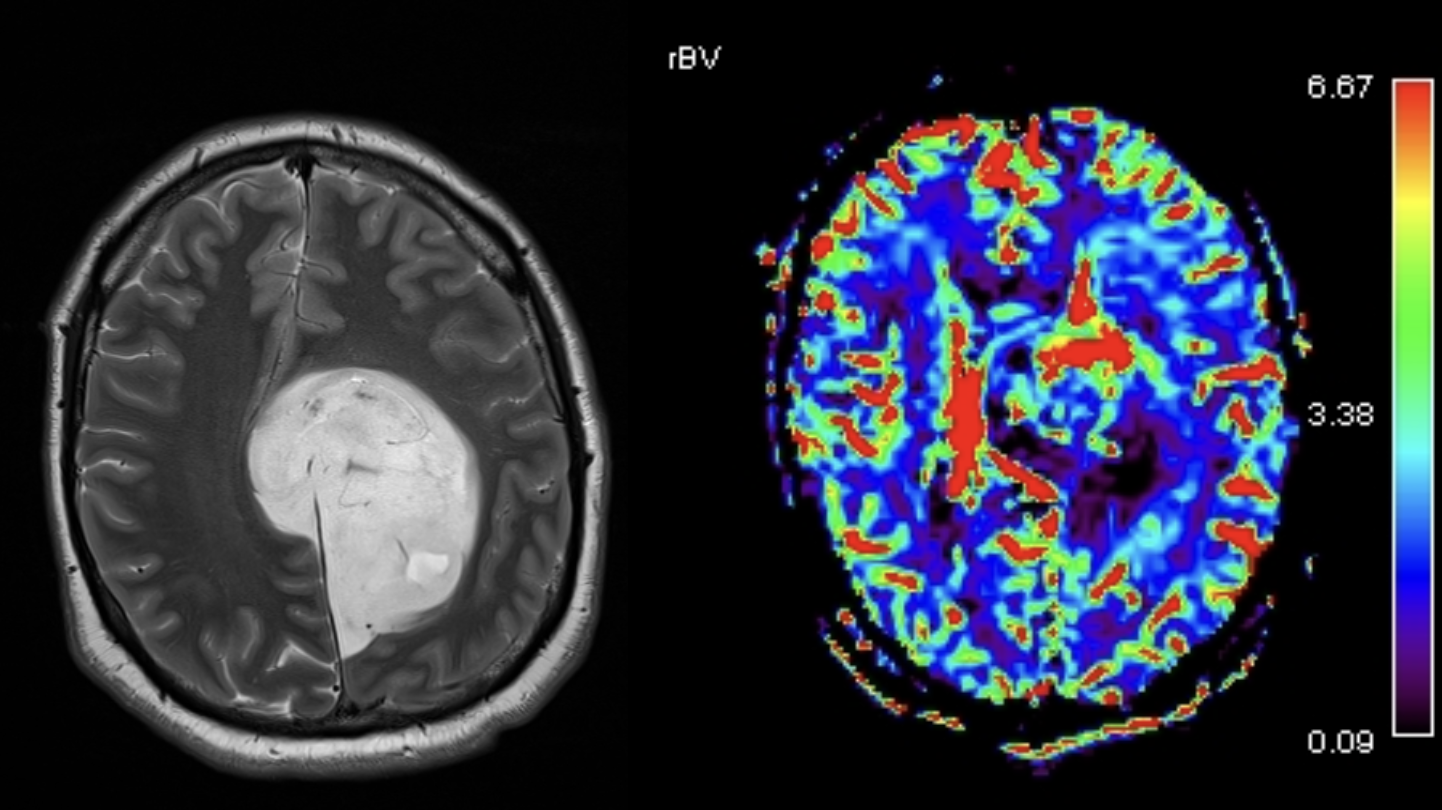

RMN-ul de perfuzie (zona marcată în roșu în interiorul tumorii) a ridicat suspiciunea unui grad de malignitate mai mare decât cel anticipat — suspiciune confirmată intraoperator: grad 3. Supraviețuirea medie în astfel de cazuri este de 2-3 ani. Pacienta depășește 5 ani de supraviețuire.